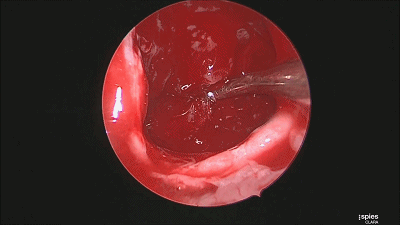

▼肿瘤切除满意后,速即纱包裹明胶海绵填塞瘤腔。

▼用纤维蛋白胶加固